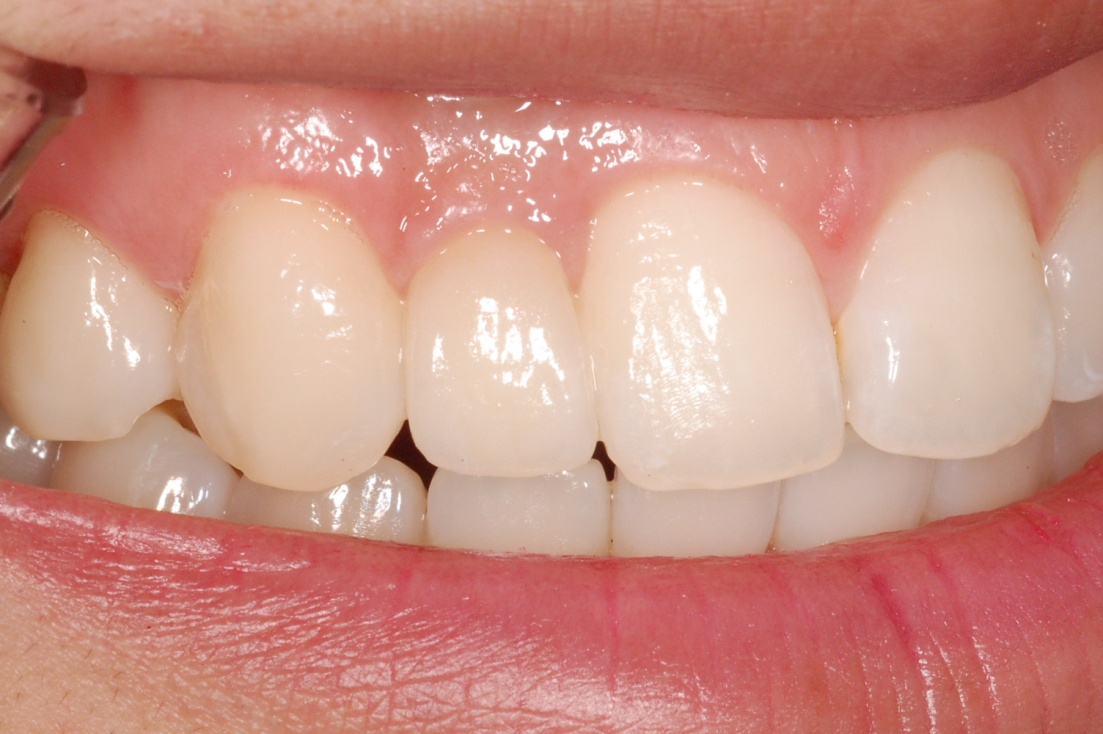

기존 보철 치료의 문제점은 인접한 자연치아를 깍아야 한다는 것입니다. 임프란트의 가장 큰 장점은 해당 부위만 치료할수 있어 주변의 소중한 자연치아를 건드리지 않는 것이 장점입니다.

왜 임플란트인가요 왜 임플란트인가요2